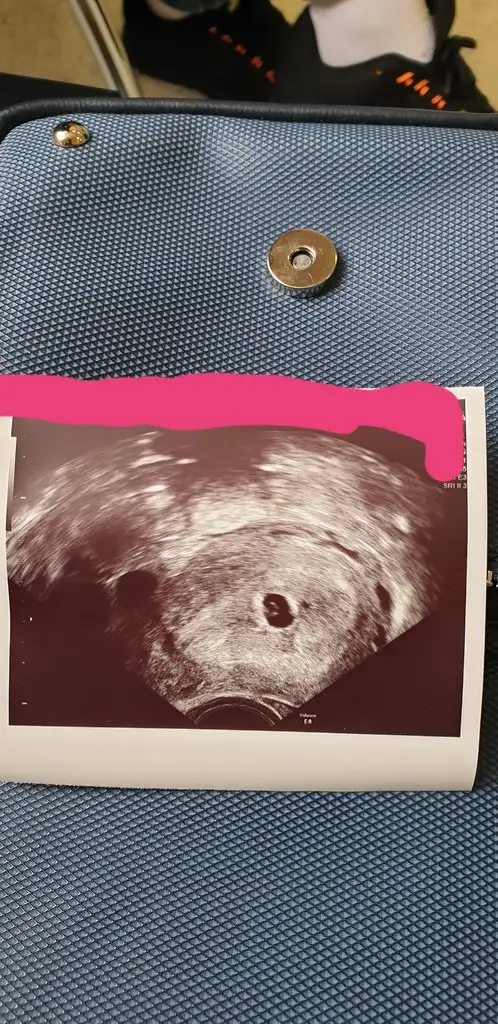

Kan testini bugun yaptirdim 185 pozitif ciktiIkinci yi gördüm . Bi kan testini yaptirsandaha emin olursun

Hayırlısı olsun cnm. Rabbım tamamını erdırsinKan testini bugun yaptirdim 185 pozitif ciktihaftaya gel dediler

Kan testini bugun yaptirdim 185 pozitif ciktihaftaya gel dediler

Benim 3. Gün embriyosu ile 1 kızım oldu 4 yaşına girdi şimdi tekrar denedik gene 3. Gün embriyosu idi pozitif çıktı daha kese görmedik inşallah hayırlısıyla hamile kalırsın canımyeterki allah ol desin

Ben 30 yaşındayım uzun protokol tedavi ile 5 adet yumurtam gelişti, yumurta toplama işleminde sadece 3 tane yumurtanın gelişmiş olduğu gördüler. Yumurta toplamanın ertesi günü embriyolog aradı ve sadece 2 yumurtanın döllendiğini söyledi. 3. Gün transfer yapılacağını bildirdi.

3. Gün embriyo transferi ile hamile kalanların desteğini almak, moral depolamak için açtım üyelik ve yazmak istedim. Çünkü zaten 30 yaşta bu kadar az yumurta olması, 2 tanecik döllenmesi beni biraz üzdü.